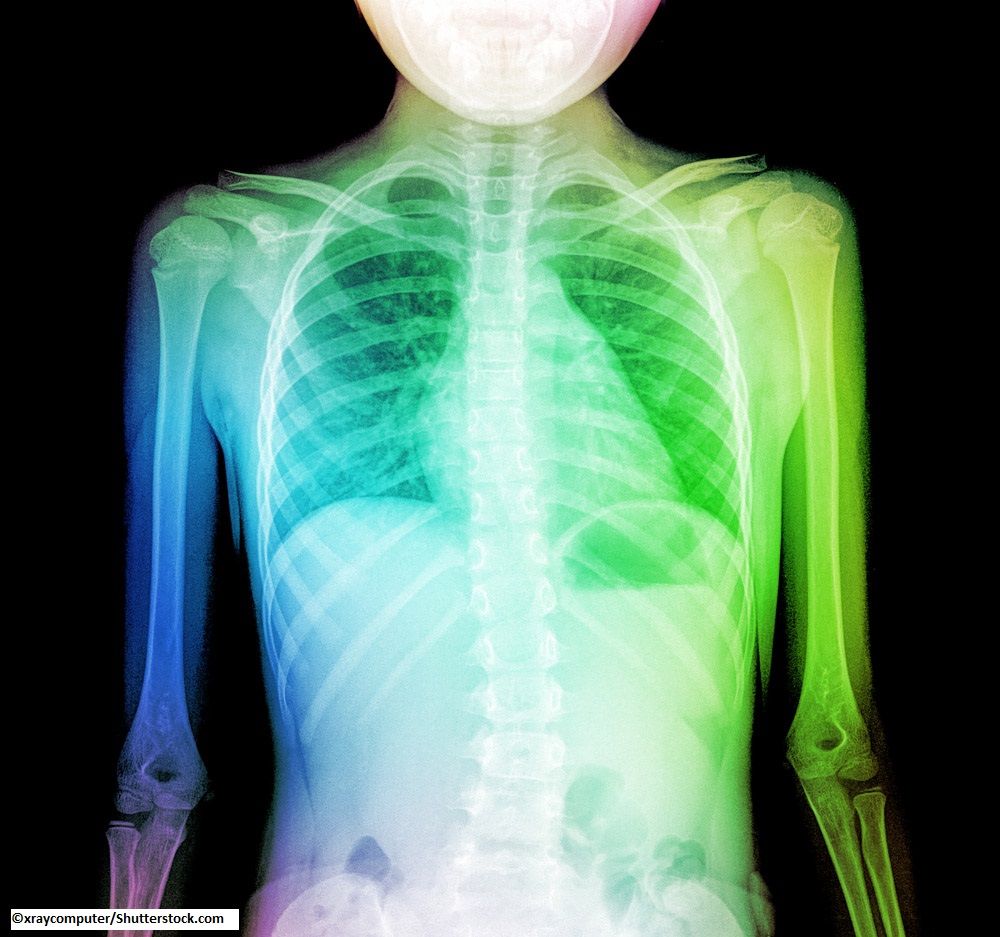

Lower respiratory infections in children seem to predispose to poor adult lung function, but causation and directionality have yet to be determined.

Early-life respiratory tract infections appear to increase the risk of asthma and worsen lung function in later life, according to a new study.

Those who had had RTI -- colds, sinusitis, laryngitis, tonsillitis, pharyngitis and otitis--by age 5 years had a 1.5-fold increased risk of asthma in later life. Children who had lower RTIs--bronchitis, bronchiolitis, pneumonia and general chest infections--had a 2- to 4-fold increased risk of asthma in later life and were also more likely to have worse lung function.

Upper RTIs were not associated with worse lung function in later life. However, lower respiratory infections at almost all ages were associated with worse lung function, as indicated by lower scores for FVC, FEV1, and forced expiratory flow at 75% of FVC.